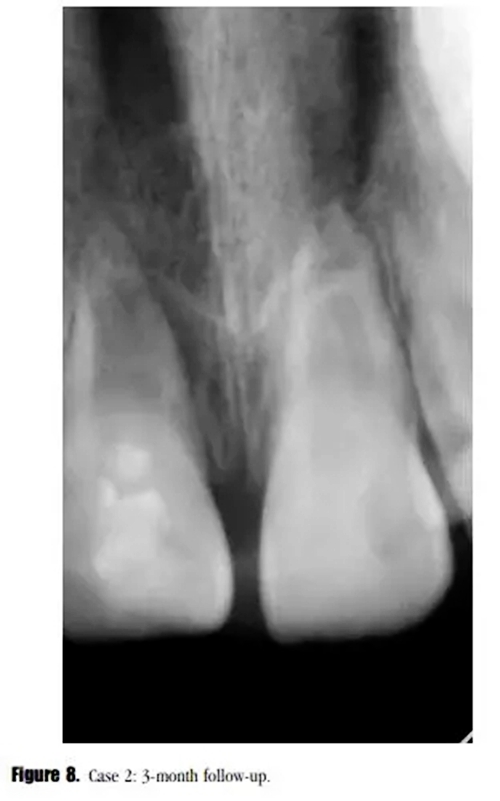

盡管在3個月的隨訪中,瘺管沒有消失,但是牙齒的癥狀已經(jīng)消失了。X線顯示根尖區(qū)的進一步發(fā)育,牙根近中方向有透射性影響。與患者家長溝通后,1個月后實行常規(guī)根管治療。根尖區(qū)放置5mm后的MTA栓,復合樹脂以及纖維加強樁修復。少量的MTA從根尖近中方向被壓出。此外,根管系統(tǒng)以及繼發(fā)生成的根尖組織之間可見一明顯的透射影像。(圖8)